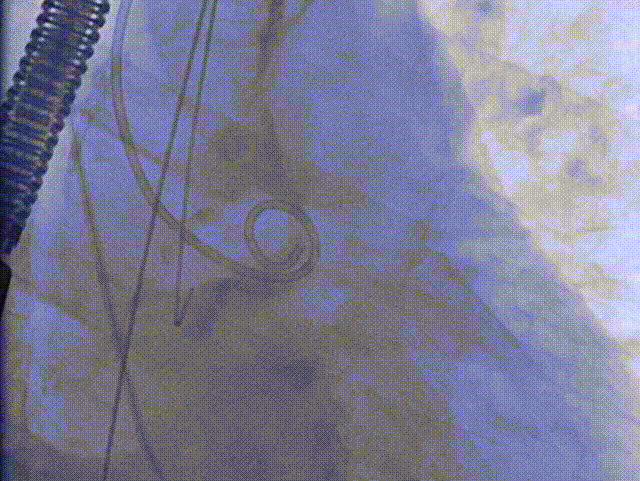

22mm球囊预扩影像示双侧冠脉灌注良好,无明显腰征,决定植入AV26号瓣膜。

造影辅助下精准释放

左侧腋动脉入路建立后,团队密切配合,高效完成了跨瓣、球囊预扩操作。22mm球扩影像示双侧冠脉灌注良好,无明显腰征,决定植入AV26号瓣膜。输送器过弓顺利。在瓣膜定位过程中,通过善用造影辅助,我们成功将瓣膜定植于预定释放位(瓣环下约3mm处)。瓣膜释放后形态规整,工作状态良好,未发生明显位移。